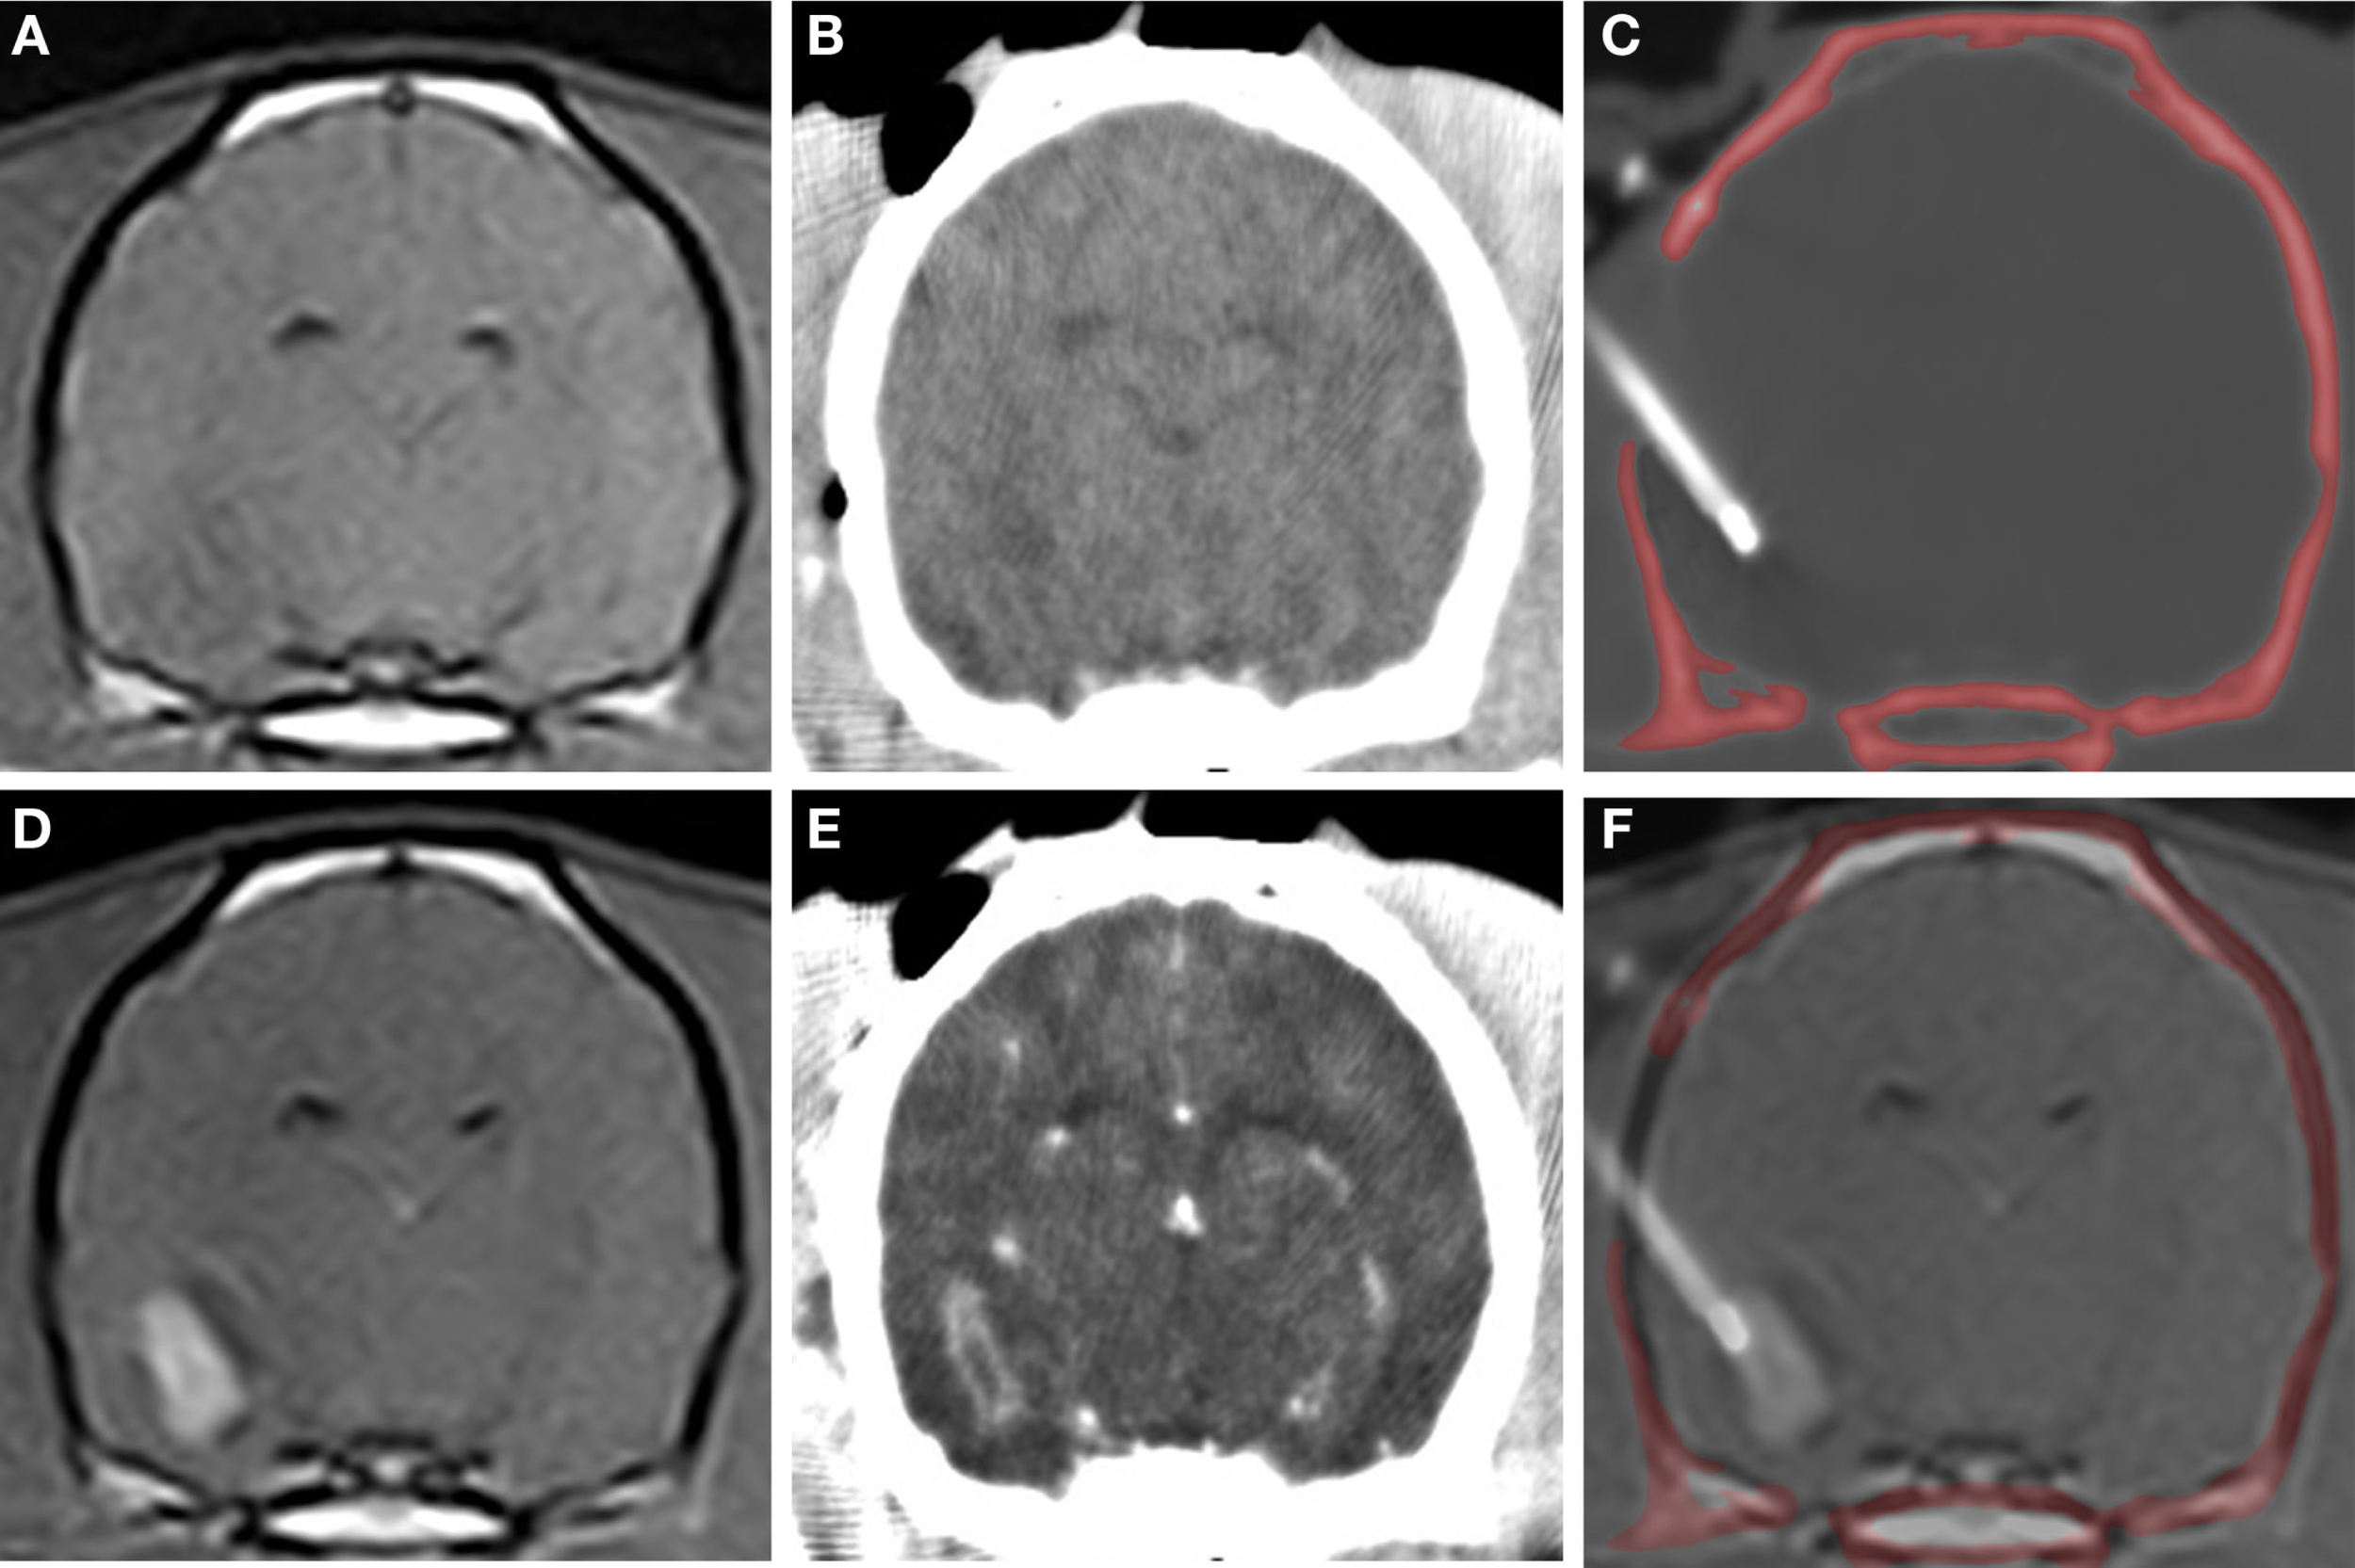

Figure 5

CT-guided stereotactic biopsy procedure in a dog with a Grade III oligodendroglioma. Transverse, pre-contrast (A,B) and post-contrast (C,D) T1-weighted MR (A,D) with corresponding stereotactic CT planning images (B,E). Intraoperative transverse CT image (C) with biopsy needle in situ. The craniectomy defect in this patient has been enlarged to accommodate placement of an implanted guide pedestal that will later be used to introduce electrodes into the tumor for therapy. Co-registered CT and MR image (F) demonstrating needle placement that includes contrast enhancing lesion and the surrounding brain.